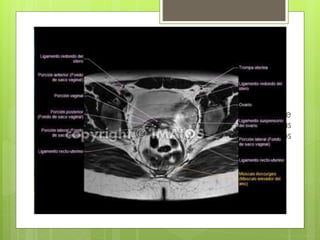

RM PÉLVICA

 Diagnosticar o reconocer la fase de anomalías de

desarrollo como leiomiomas, adenomiosis, neoplasias

vaginales, carcinoma cervical o endometrial, ovarios

poliquísticos u otras masas ováricas.

RM PÉLVICA  Diagnosticaro reconocer la fase de anomalías de desarrollo como leiomiomas, adenomiosis, neoplasias vaginales, carcinoma cervical o endometrial, ovarios poliquísticos u otras masas ováricas.